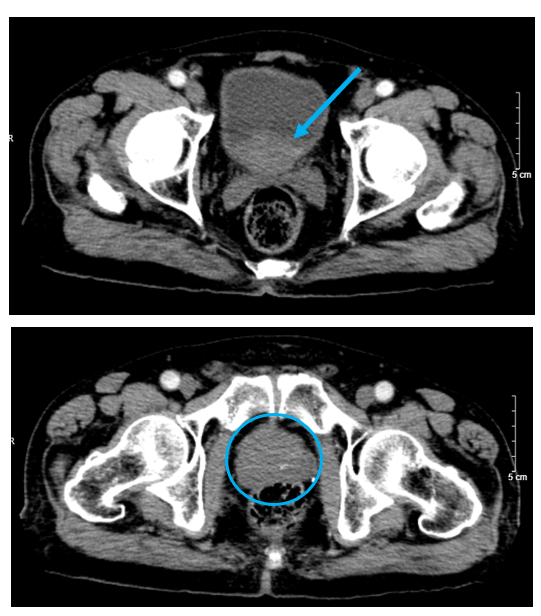

Hình 8. Hình ảnh não không có khối choán chỗ trong thời gian điều trị (mũi tên xanh) và não xuất hiện khối u di căn não thùy trán phải cạnh sừng trán não thất bên, kích thước 14×22 mm sau khi bỏ điều trị 3 tháng (mũi tên đỏ), trên phim cộng hưởng từ sọ não tại mặt phẳng axial.